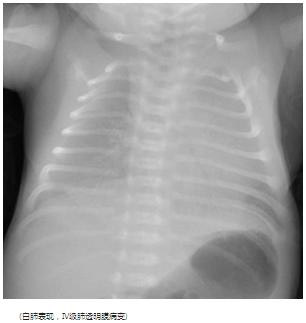

典型胸片结果: